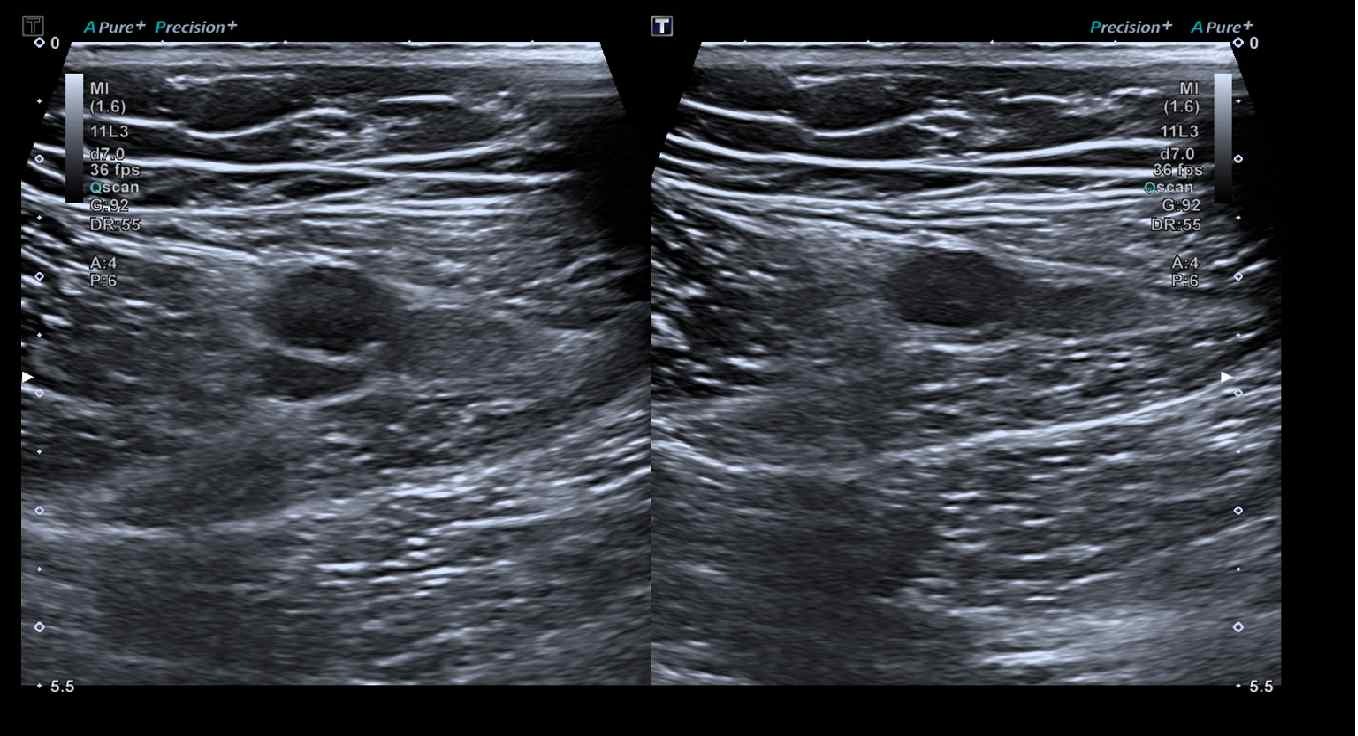

ECO Flebografía MMII: Aumento del diámetro en vena femoral superficial, poplítea, tibial posterior y gemelares con presencia de material ecogénico en su interior, carencia de compresibilidad y ausencia de flujo doppler, compatible con trombosis venosa profunda.

Se confirma el diagnóstico y desde urgencias se inicia anticoagulación con sintrom y heparina por 5 días, con control por equipo Atención Primaria. Se da de alta hospitalaria.